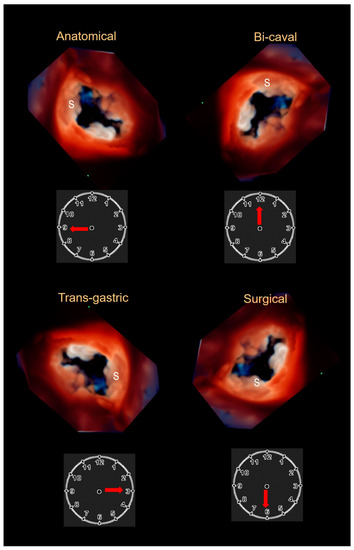

2.3. Echocardiography

- Hahn, R.T.; Nabauer, M.; Zuber, M.; Nazif, T.; Hausleiter, J.; Taramasso, M.; Pozzoli, A.; George, I.; Kodali, S.; Bapat, V.; et al. Intraprocedural Imaging of Transcatheter Tricuspid Valve Interventions. JACC Cardiovasc. Imaging 2019, 12, 532–553. [Google Scholar] [CrossRef] [PubMed]